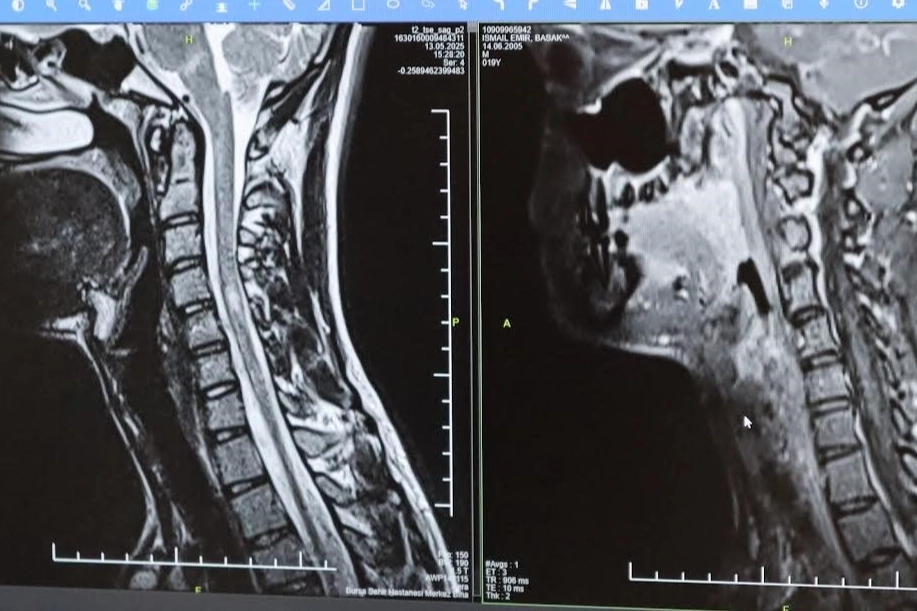

Bursa Şehir Hastanesinde görevli Nöroloji Uzmanı Prof. Dr. Özden Kamışlı, 30 Mayıs Dünya MS Günü kapsamında açıklamalarda bulundu. MS’in, bağışıklık sisteminin sinir sistemine saldırmasıyla gelişen kronik bir hastalık olduğunun bilgisini veren Prof. Dr. Kamışlı, "Dünyada yaklaşık 2.8 milyon MS hastası olduğu bilinmektedir. MS genellikle 20-40 yaş arası gençleri etkilemektedir. Bununla birlikte çocukluk döneminde ya da ileri yaşta da ortaya çıkabilmektedir. Kadınlarda görünme sıklığı erkeklere göre bir buçuk kat daha fazladır" dedi. MS hastalarının çeşitli şikâyetlerle hekimlere başvurduğunu vurgulayan Kamışlı, "Bunlar arasında görme bozukluğu, kol ve bacakta kuvvetsizlik, uyuşmalar, dengesizlik, yürüme bozukluğu, idrar problemleri veya aşırı yorgunluk ve halsizlik hali bulunmaktadır. MS ataklarla seyredebilir ve genellikle en sık görülen formu budur. Birdenbire bir şikâyet ortaya çıkar ve zamanla azalır veya kaybolur. Bir de progresif dediğimiz ilerleyici formu vardır. Bu ilerleyici formda hastalık yavaş yavaş ilerlemektedir. MS her hastada farklı seyreder. Bu nedenle tek tip bir MS hastalığından bahsetmek mümkün değil" şeklinde konuştu.

TEDAVİDE GELİŞME KAYDEDİLDİ Hastalığın tanısını ne kadar erken konulursa ve tedaviye ne erken başlanırsa; hastaların günlük hayatta aktif ve üretken bir şekilde devam etmelerinin o kadar kolaylaştığına dikkat çeken Kamışlı, "Günümüzde MS'le ilgili çok fazla gelişme oldu ve tedavi seçenekleri arttı. MS merkezlerinde bu tedavi seçeneklerine ulaşmaları mümkün. Hastalarımız için doğru tanı, düzenli takip ve uygun tedavi oldukça önem teşkil etmektedir" diye konuştu.